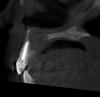

kenig Опубликовано 18 октября, 2012 Поделиться Опубликовано 18 октября, 2012 (изменено) Июль 12г.Жалобы:постоянный привкус гноя во рту, по утрам под губой белый сгусток, каждые три дня распухает небо, при нажатии на небо выделяется гной в области 12 зуба.Объективно:11 зуб покрыт исскуственной коронкой, 12 временная реставрация (находится на этапе лечения), 13 зуб интактный. В области 12 зуба с вестибулярной стороны свищ.R-гр.: киста вобласти 11,12,13 зубов.Анамнез: 12 зуб лечат год в другом лечебном учреждении, безуспешно, ничего не меняется.Рекомендовано:КТ верхней челюстиЭндо-лечение 11,12,13 зубов. Проведено лечение 11 зуба-коффердам, хлорка, лимонка, каласепт на две недели,пломбирование-вертикалка. Результат-пациент счастлив-привкус гноя пропал, под губой по утрам ничего нет, распухает раз внеделю. Свищ на месте. Проведено лечение 13 зуба-коффердам, хлорка, лимонка,каласепт на две недели, пломбирование-вертикалка. Все это время 12 зуб моем, моем,но из него все время льется, хотя через 10-20 минут мытья его возможно высушить.Результат-еще лучше, распухает раз в две недели. Свищ на месте..Сентябрь-наконец-то принесли КТ-ужас. В процессе небный корень 14 зуба, хотя реагирует на холод как витальный зуб. Небно нет кости от 11 до 14 зуба, в области 11 зуба сообщение с полостью носа. Вопросы:Эндо 14 зубу проводить? Реагирует на холод, как живой.12 зуб пломбировать? Просушить его возможно через минут 10-20 мытья. Временные промежутки между обострениями увеличиваются, но меня результат не радует.Как бы поступили Вы в такой клинической ситуации? -диагностический 12 зуба-контрольный 11 зуба-контрольный 13 зуба-КТ 11 зуба-КТ 12 зуба-КТ 13 зуба-КТ 14 зуба был подобный случай, причинный был 22, эндо с апексификацией 22, гидроокись не приносила ожидаемых результатов, раз 5 получал несколько 2-кубовых шприца желтой опалесцирующей жидкости, потом высушил, запаковал МТА, хоирург сделал декомпрессию по парч, полтора года мыли хлоргексидином раз в 2 недели, вот что получилось, без всякой хирургии Изменено 18 октября, 2012 пользователем kenig 1 Ссылка на комментарий

kenig Опубликовано 20 октября, 2012 Поделиться Опубликовано 20 октября, 2012 И что дальше?! Или лечение закончено?! И скока оно, лечение будет продолжаться?! Дальше просто убрали дренаж и все. Проводится дальнейшая санация. КТ контроль через 1 год, думаю что там будет костная ткань. Ссылка на комментарий